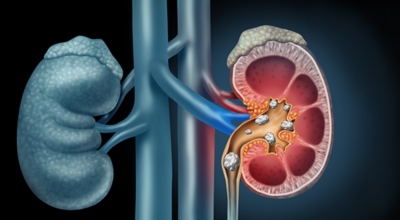

요로결석이란

수분 섭취 감소는 요로결석의 가장 주요한 발병 이유가 되는 것 이라고 하네요. 수분의 섭취가 떨어지면 요석결정이 소변에 머무르는 시간이 길어져 요석형성이 증가하게 되며 요로결석의 발생은 유전적인 소인이 있다는 것이 정설이나 후천적인 생활습관도 연관성을 보입니다.

남성이 여성에 비교해 2-3배 발생 위험성이 높고, 20~40대의 젊은 연령층에서 잘 발생하였다고 하나 최근 고령층에서 발생이 증가하고 있고 요로결석은 지리적으로 산이 많은 지역, 사막, 열대 지방에서 많이 생기는데, 이는 음식, 온도, 습도 등이 복합적으로 작용하기 때문이라고 합니다. 온도와 계절은 요로결석 발생에 주요한 요인으로 작용하지만, 여름에는 땀을 많이 흘리면서 소변이 농축되어 요로결석의 생성이 용이해진다고 합니다.